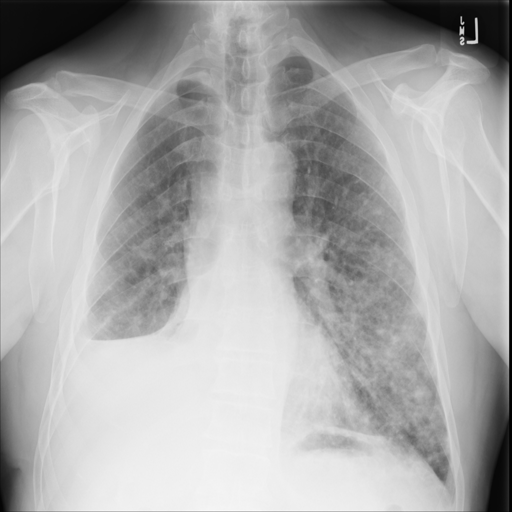

图片示例: